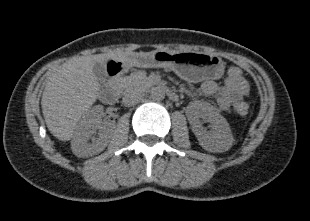

Методика КТ позволяет оценить анатомическое строение почек, надпочечников, состояние мочеточников и мочевого пузыря, кроме того, дает возможность визуализировать сосудистую систему и регионарные лимфатические узлы.

Сканирование применяется для выявления воспалительных заболеваний почек, чашечно-лоханочной системы, мочеточников и мочевого пузыря, также позволяет обнаружить конкременты на фоне мочекаменной болезни, диагностировать доброкачественные и злокачественные новообразования, точно классифицировать кистозные образования по системе Bosniak, что особенно важно для урологов и нефрологов, а также определить степень поражения регионарных лимфатических узлов. Кроме того, КТ используется для диагностики травматических повреждений органов мочевыделения, аномалий развития почечно-лоханочной системы, дает максимальную информацию для хирурга при планировании оперативного вмешательства.

В случае необходимости информативность исследования может быть увеличена за счет контрастного усиления. Чаще всего эта методика применяется для диагностики опухолевых процессов. Йодсодержащий контрастный препарат вводится внутривенно и в большом количестве накапливается в опухолевых узлах благодаря тому, что опухоли имеют хорошо развитую систему кровоснабжения.

Контраст активно поглощает рентгеновские лучи, поэтому патологические образования становятся хорошо видны на снимках. Это позволяет выявлять опухоли минимальных размеров. Кроме того, с помощью контрастного усиления можно определить точные размеры и границы опухоли, оценить степень прорастания ее в соседние органы и ткани, обнаружить поражение регионарных лимфоузлов. Применение контрастирования также помогает отличить доброкачественные опухоли от злокачественных, выявить воспалительные изменения почек, чашечно-лоханочной системы, мочеточников и мочевого пузыря.

Что показывает КТ почек, мочеточников, мочевого пузыря

- опущение почек;

- аномалии развития почек, мочетоников

- доброкачественные и злокачественные новообразования;

- камни (конкременты);

- уретероцеле

- сосудистую патологию (сосудисто-мочеточниковый конфликт, инфаркт почки);